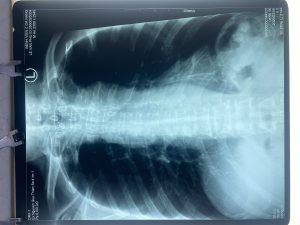

MỘT SỐ HÌNH ẢNH TRONG QUÁ TRÌNH ĐIỀU TRỊ BỆNH NHÂN

Hình 1. Ung thư loét sùi chảy máu, hẹp lòng thực quản, ống soi không qua được chỗ hẹp